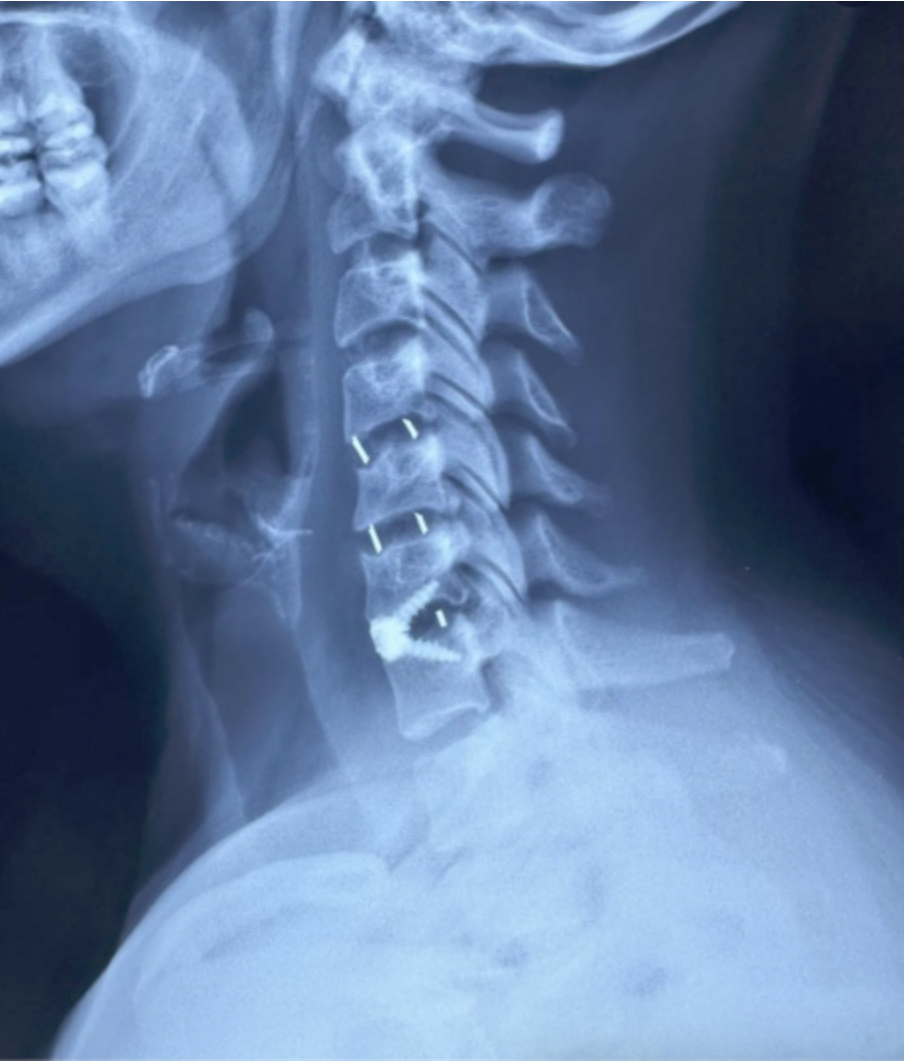

La cirugía de columna es una rama altamente especializada enfocada en el tratamiento de patologías que afectan la estabilidad, movilidad y funcionalidad de la columna vertebral, incluyendo hernias discales, estenosis espinal y enfermedades degenerativas.

Cada procedimiento requiere una planificación detallada, basada en estudios de imagen y evaluación clínica, con el objetivo de lograr una descompresión adecuada de estructuras nerviosas y restaurar la estabilidad vertebral.